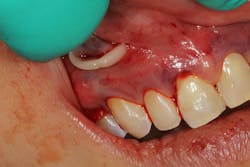

PRF is an autogenous biomaterial derived from the patient’s blood. It is rich in growth factors and cytokines that accelerate tissue repair, angiogenesis, and wound healing. When combined with PST, PRF acts as a natural scaffold, promoting soft-tissue healing, maintaining tissue volume, and potentially reducing gingival inflammation. PRF’s bioactive properties allow for improved attachment of gingival tissues and greater stability in areas of multiadjacent recession (figures 3–5).

Recent advancements in combining PRF (i.e., Bio-PRF) with PST have shown increased effectiveness in root coverage, enhanced gingival thickness, and better postoperative outcomes when compared to PST alone (figure 6).